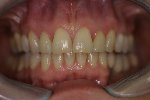

- Komplette Regeneration der Pappille 3 Monate nach der Eingliederung der Implantatkrone

- Vollkeramische Restauration auf Implantat